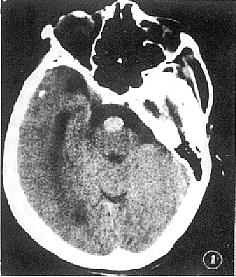

例1 女性,64岁,因头晕、呕吐伴流涎1 d就诊。既往高血压病史10余年。体检除右侧周围性面瘫外,余无阳性所见。头部CT增强加薄层扫描,于脑桥前池内见一均匀强化的血管影,为异常扩张的基底动脉,直径达1.5 cm(图1)。余脑组织未见异常。CT诊断基底动脉异常扩张症。经外院脑血管造影及DSA检查证实。

图1 增强扫描,见基底动脉异常扩张,直径达1.5 cm